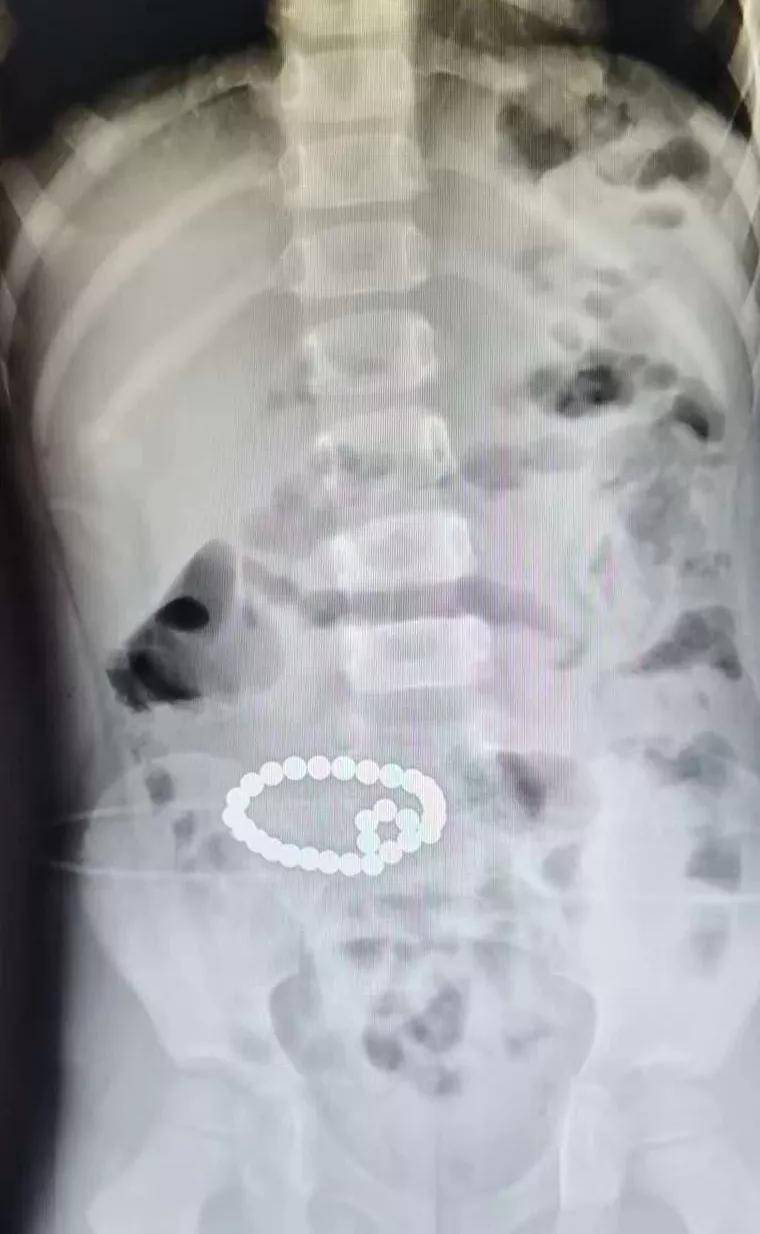

看过一个很是吓人的新闻 , 一个6岁小男孩的X光片显示 , 孩子肚子里竟然有一串“项链” 。

文章图片

谁能想到这竟是孩子误食的磁力珠 , 整整29颗紧紧连在一起 , 导致男孩腹痛了两天 , 家长却没人知道原因 , 差点就肠穿孔致命 。